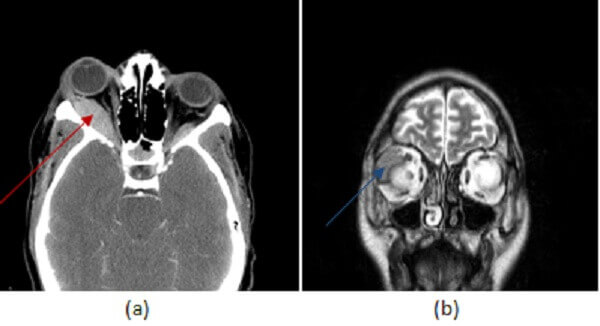

Figure 1: (a,red arrow) post contrast head CT demonstrates a smoothly marginated homogenously hyperdense extraconal mass, inseparable from the adjacent lateral rectus muscle. (b,blue arrow) Coronal T2 and (c, green arrow) axial postcontrast fat saturated T1 brain MR images in another patient with lymphoma demonstrate a tubular homogenously T2 hypointense and enhancing mass in the right lateral extraconal space that incorporates the lacrimal gland. These findings are most consistent with orbital lymphoma given the history.